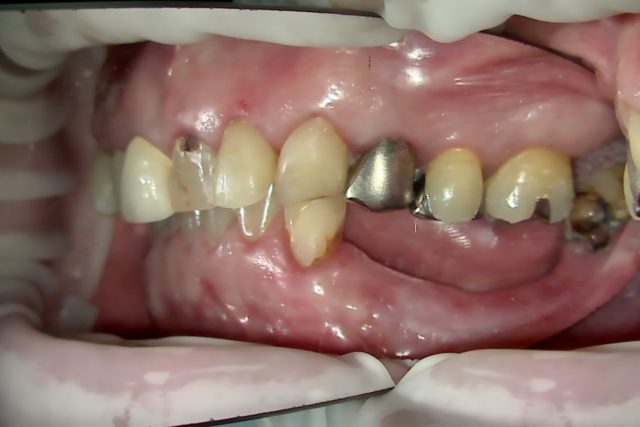

BEFORE